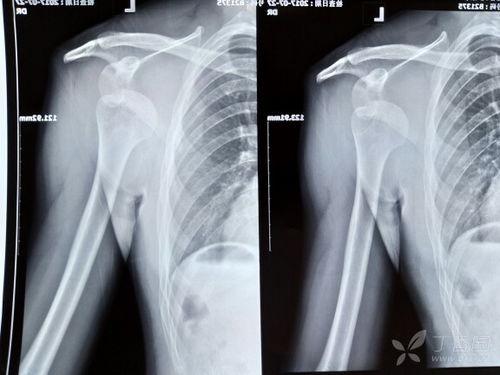

1. 观察姿势:在视频开头,医生或康复师会先观察宝宝的肩关节姿势,分析问题所在。这个过程很重要,因为只有准确判断问题,才能进行有效的复位。